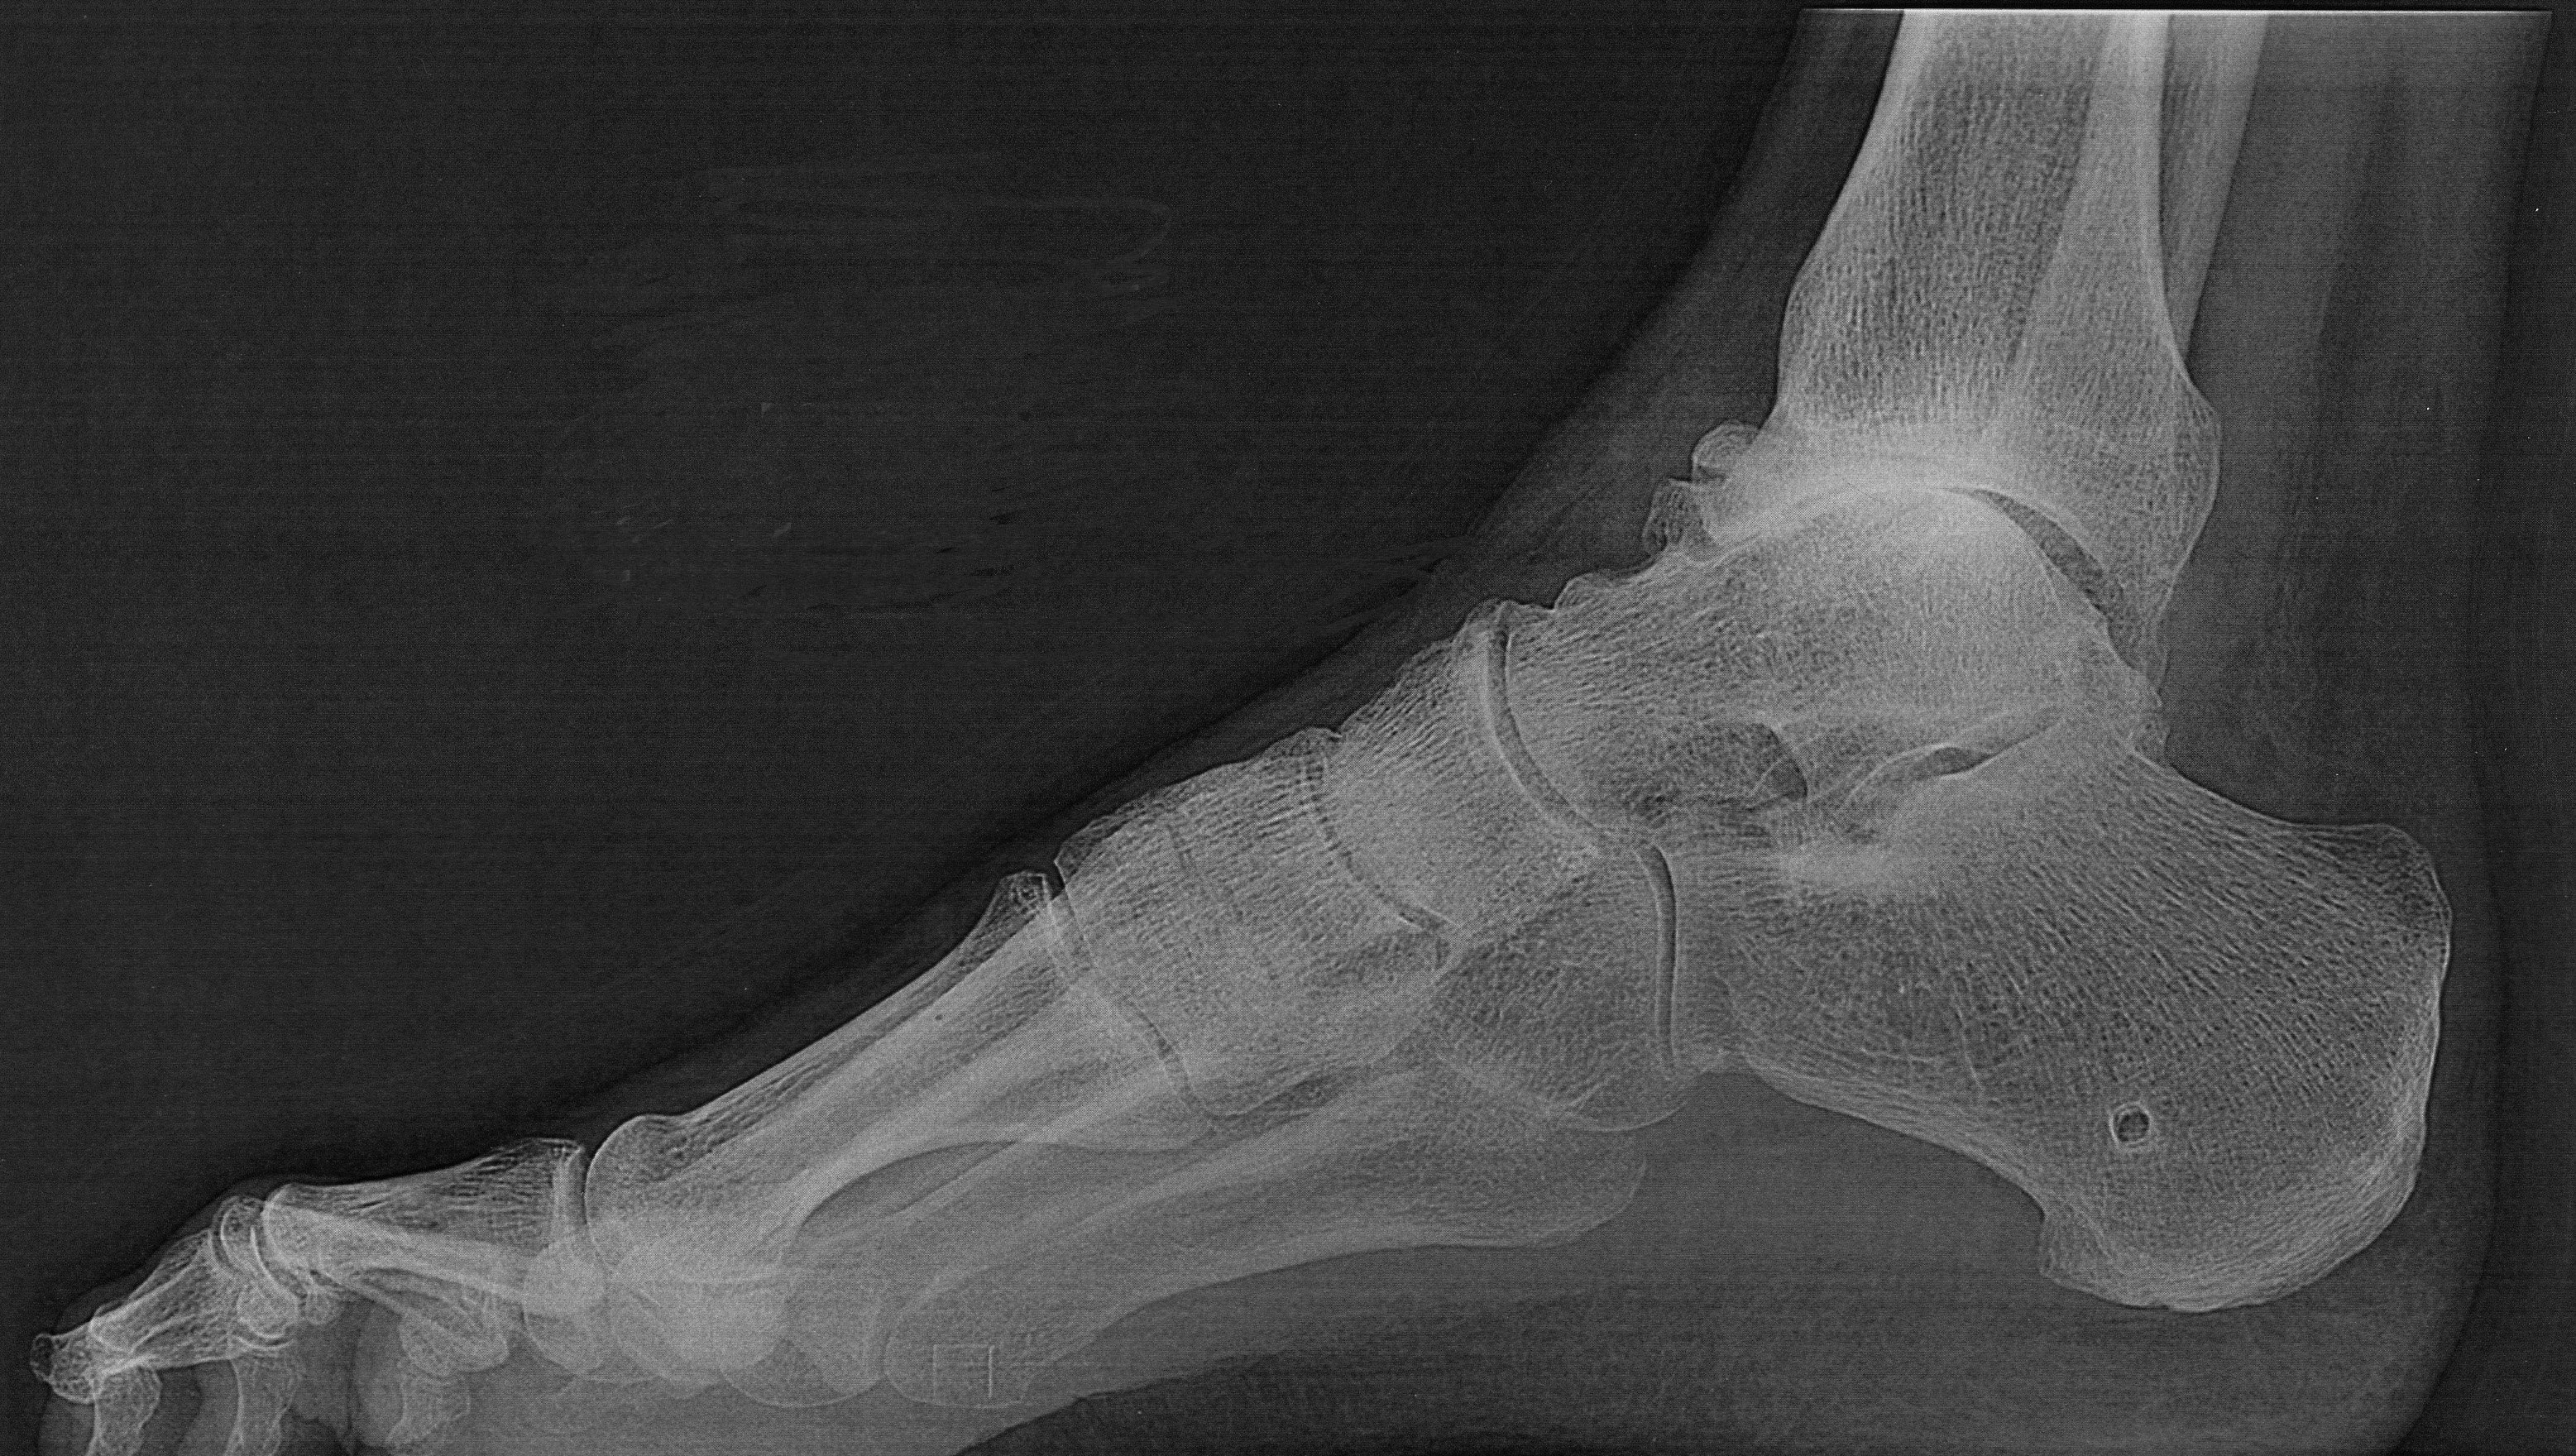

Avant...Après (vue de coté)

Cliquer sur la photo